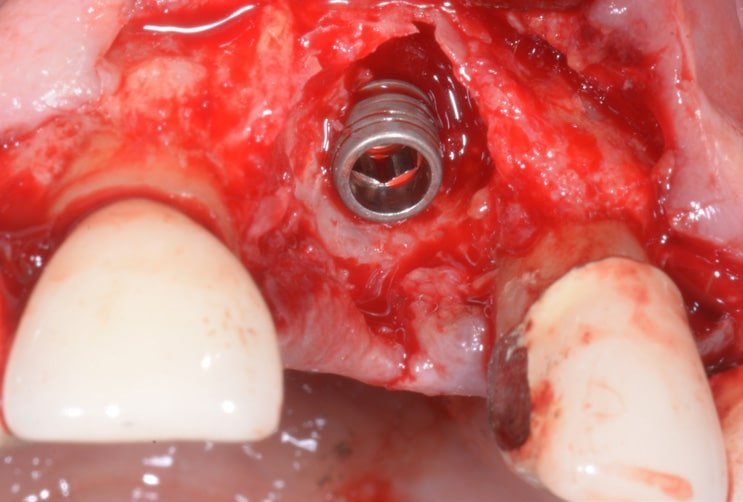

Extraction of a compromised central incisor, cleaning of the alveolus and insertion an EV line implant – self-tapping thread, under-prepared osteotomy – in the post-extraction phase for better maintenance of the bone volume.

Since the implant has no vestibular bone, it was decided to insert some bone regeneration material and cover everything with a T-barrier collagen membrane for better healing and maintenance of the tissues.